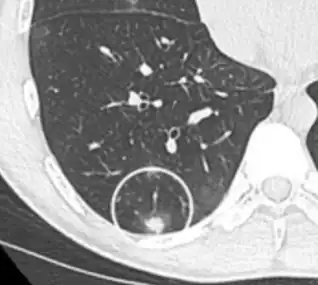

CT image showing ground-glass opacification in the posterior of the right lung (screen left). - Measles

CT image showing diffuse GGOs throughout both lungs. An abscess is also noted in the right lung (screen left). - Adenocarcinoma in situ of the lung

CT image showing ground-glass nodule (circled).